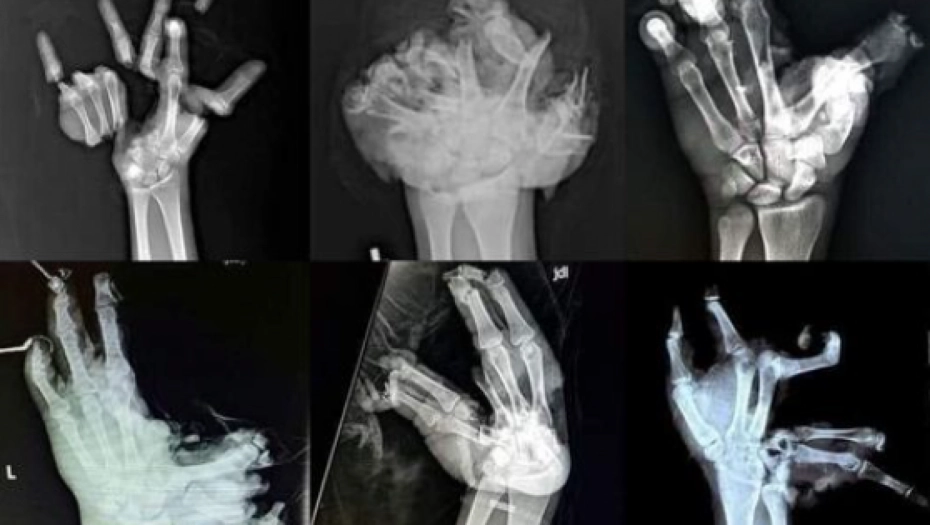

- 10 godina smo suprug i ja radili u hitnoj pomoći. Sa nelagodom očekujemo raspored dežurstva jer ni jedan zdravstveni radnik ne veseli se tom dežurstvu ... I tada stiže taj 31.12 .Obično je šaka u najlonu i ručniku iz kojeg curi krv i padaju komadi kosti i kože po čekaonici zbog nespretnog pridržavanja uplakanih roditelja ili prijatelja koji su u strašnom šoku.Nesretnik je potpuno bijel od šoka, boli i na rubu nesvestice. Moram reći da je u živo i u boji 1000 puta strašnije+bol neizdrživa, sledi brzi transport, komplikovane operacije ako se uopšte i jedan prst da spasiti. Za sekund euforije praska, plaćati će invalidnošću za celi život . Zbogom sport, zbogom vožnja, zbogom društvo , devojke, zbogom posao.Najčešće je otac zaslužan bio da se u detetovoj ruci našla petarda. Zato ako volite sebe i ostale, uživate u životu. Imate divne planove, prijatelje i sretan i bezbrižan život tada petarde prepustite onima koji su odlučili biti nepovratno nesretni.